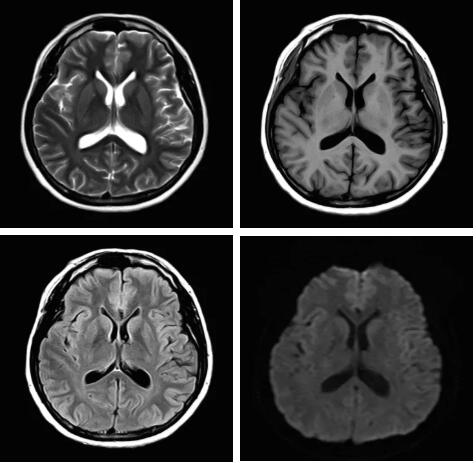

圖:Pure射頻成像鏈的優(yōu)化和改進使信噪比提升

從成像源頭的磁體采用鍍膜新磁體高密度薄層鍍膜貼合技術(shù),獲得更好的磁場均勻度,奠定磁共振成像基礎(chǔ);采用3D RSCE微雕梯度精準(zhǔn)控制頻率和相位,輸出理想波形,實現(xiàn)渦流的“0”殘余,還原最真實的圖像信息;射頻接收端通過計算機人工智能對信號抗干擾處理,把信號放大并去除梯度、磁場等對信號干擾,再經(jīng)過二次人工智能信號識別,去除噪聲污染獲得純凈的信號;通過Pure射頻成像鏈的優(yōu)化和改進使信噪比提升40%,這是磁共振領(lǐng)域革命性的顛覆和改變。